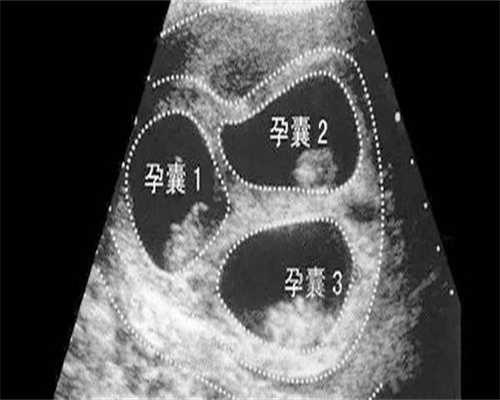

黄金准备期通常需要14-21天完成内膜转化:

- 前10天使用雌激素促进内膜增生(理想厚度7-14mm)

- 后4-5天添加孕酮诱导分泌期转化,助力代怀产子